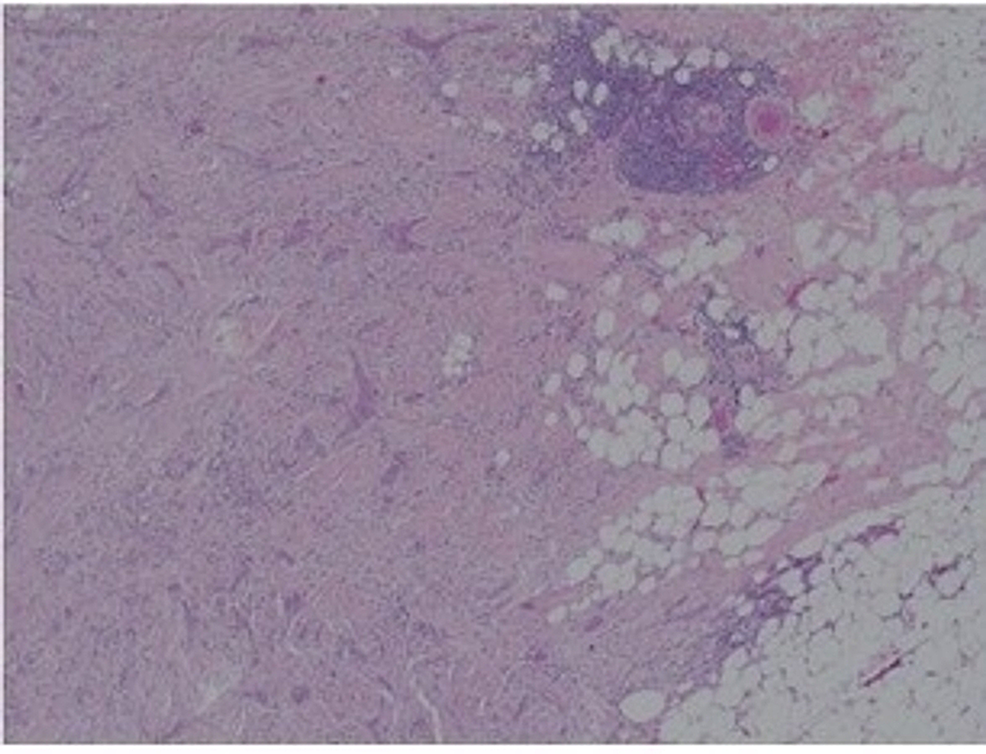

Mammogram (Figure 1) showed a 25-mm suspicious lesion in the right axillary tail, which was also visualized on ultrasound (Figure 2), along with a suspicious lymph node in the right axilla. Imaging-guided core biopsies were taken from both; the histopathology was consistent with grade 1 invasive ductal carcinoma, and ER 0, PR 0, and HER 2 negative as well. Mastectomy with axillary clearance was performed after consultation with breast MDT (multidisciplinary team). The post-operative histopathology revealed 23-mm, grade I, triple-negative invasive ductal carcinoma (Figure 3) with lymphovascular invasion, Ki67 10%, one out of nine lymph nodes showing metastatic disease, and the final staging as T2N1M0. The MDT advised for annual surveillance for five years.